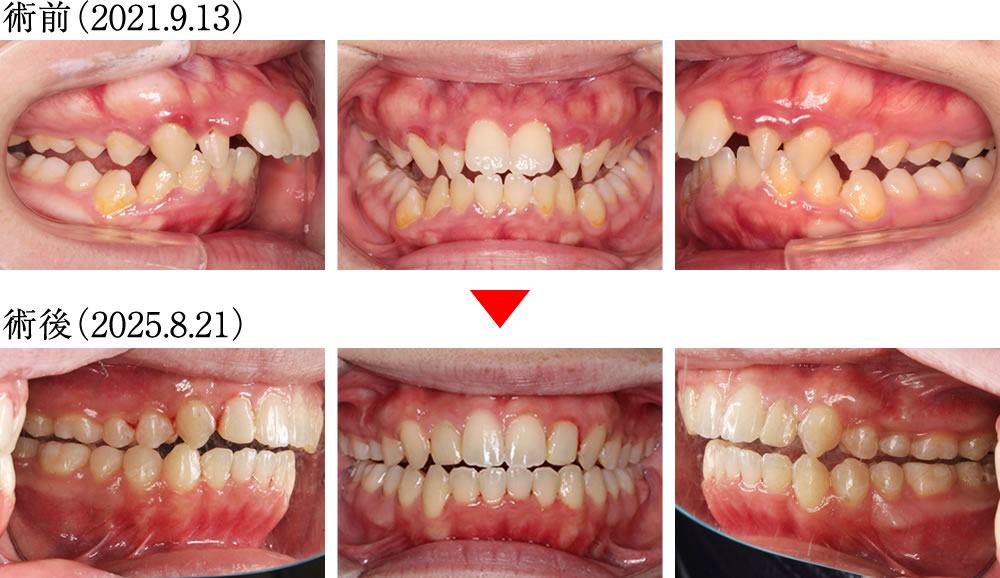

術前は、深い噛み込みと前方に大きく傾斜した前歯により、咬合不良を伴う歯並びでしたが、術後は上下の歯が理想的な傾斜と被蓋関係で噛み合い、整った美しい歯並びになりました。

歯列が拡がったことにより、バッカルコリドー(笑った際に上の歯列と頬の内側との間にできる「黒い影」)が大きく改善されました。

術前は、歯列が狭く、不均衡に乱れたアーチの歯並びでしたが、術後は歯が理想的に配列し、整った大きなアーチになりました。